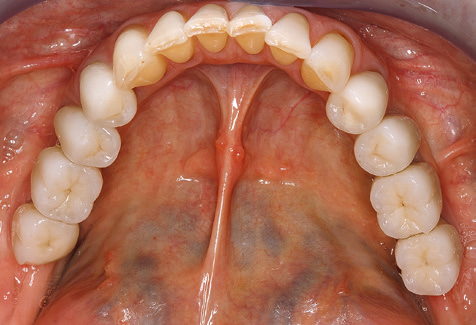

A 52-year-old patient presented in our clinic for the first time in 2004 following tooth loss in the third quadrant, expressing a desire for a new prosthetic restoration. Periodontal and radiological diagnostics revealed the need for extensive periodontological treatment. In addition, teeth 48, 28 and 27 were attributed a very poor prognosis and were subsequently extracted (Fig. 1). Following the successfully completed, systematic periodontological treatment, a fixed dental implant was inserted with the introduction of five implants in tooth regions 35, 36, 37, 46 and 47. Prosthetic treatment of the natural teeth was effected with veneered zirconium dioxide ceramic crowns; the implants were composed of two-piece, individual zirconium dioxide abutments and similarly veneered crowns made of a zirconium dioxide ceramic (Cercon base colored, Dentsply Sirona Lab). Definitive insertion of the prosthetic restoration occurred in 2005.

Standardised and regular risk-adapted care in the scope of SPT is the key to treatment success for the clinical long-term success in periodontically compromised patients. This is particularly true for patients fitted with implants following successfully completed periodontal treatment (Fig. 11a and b).